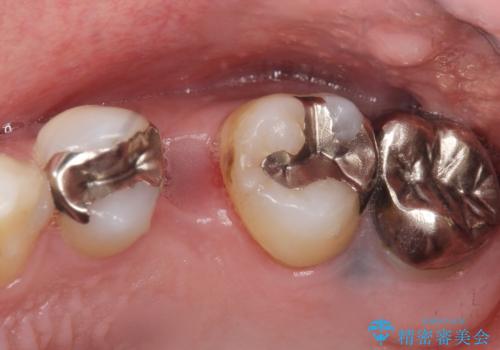

- インプラント治療のついでに、銀の詰め物を白くしたいとご希望された患者様です。

痛みやしみるなどの症状はありませんでしたが、銀の詰め物を除去したところう蝕を認めました。

う蝕を丁寧に除去したのち、セラミックインレーによる修復を行いました。